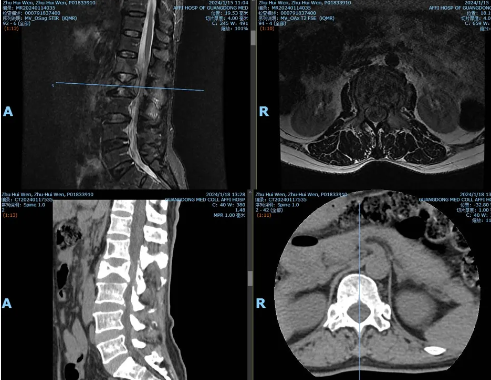

·患者朱某某,女,58岁,因反复腰背部疼痛半年,加重1周入院。腰背痛VAS评分7分。

·诊断:1.腰2椎体转移瘤(ESCC,2级);2.肺癌

智能控温射频消融能明显减少瘤体出血量(出血量50ml),为分离手术提供操作基础,降低输血依赖。分离手术实现充分减压,为后续放疗治疗提供可能性。